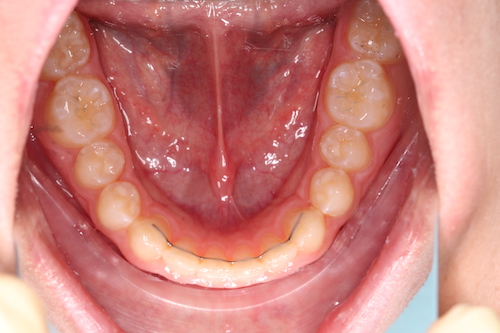

Частая ситуация, когда в общем все не плохо, но чего- то не хватает для идеала. Основной жалобой пациента было наличие выраженных промежутков на верхней челюсти, неровность положения зубов, глубокое перекрытие передних нижних резцов. Причина наличия промежутков заключалась в недостаточном размере по ширине боковых резцов верхней челюсти. именно поэтому после подъема высоты прикуса, нормализации наклонов зубов в переднем отделе, коррекции высоты перекрытия резцов, и доведение идеальных контактов в боковых отделах мы увеличили размер боковых резцов за счет композитного материала. Срок лечения 1 год.

До